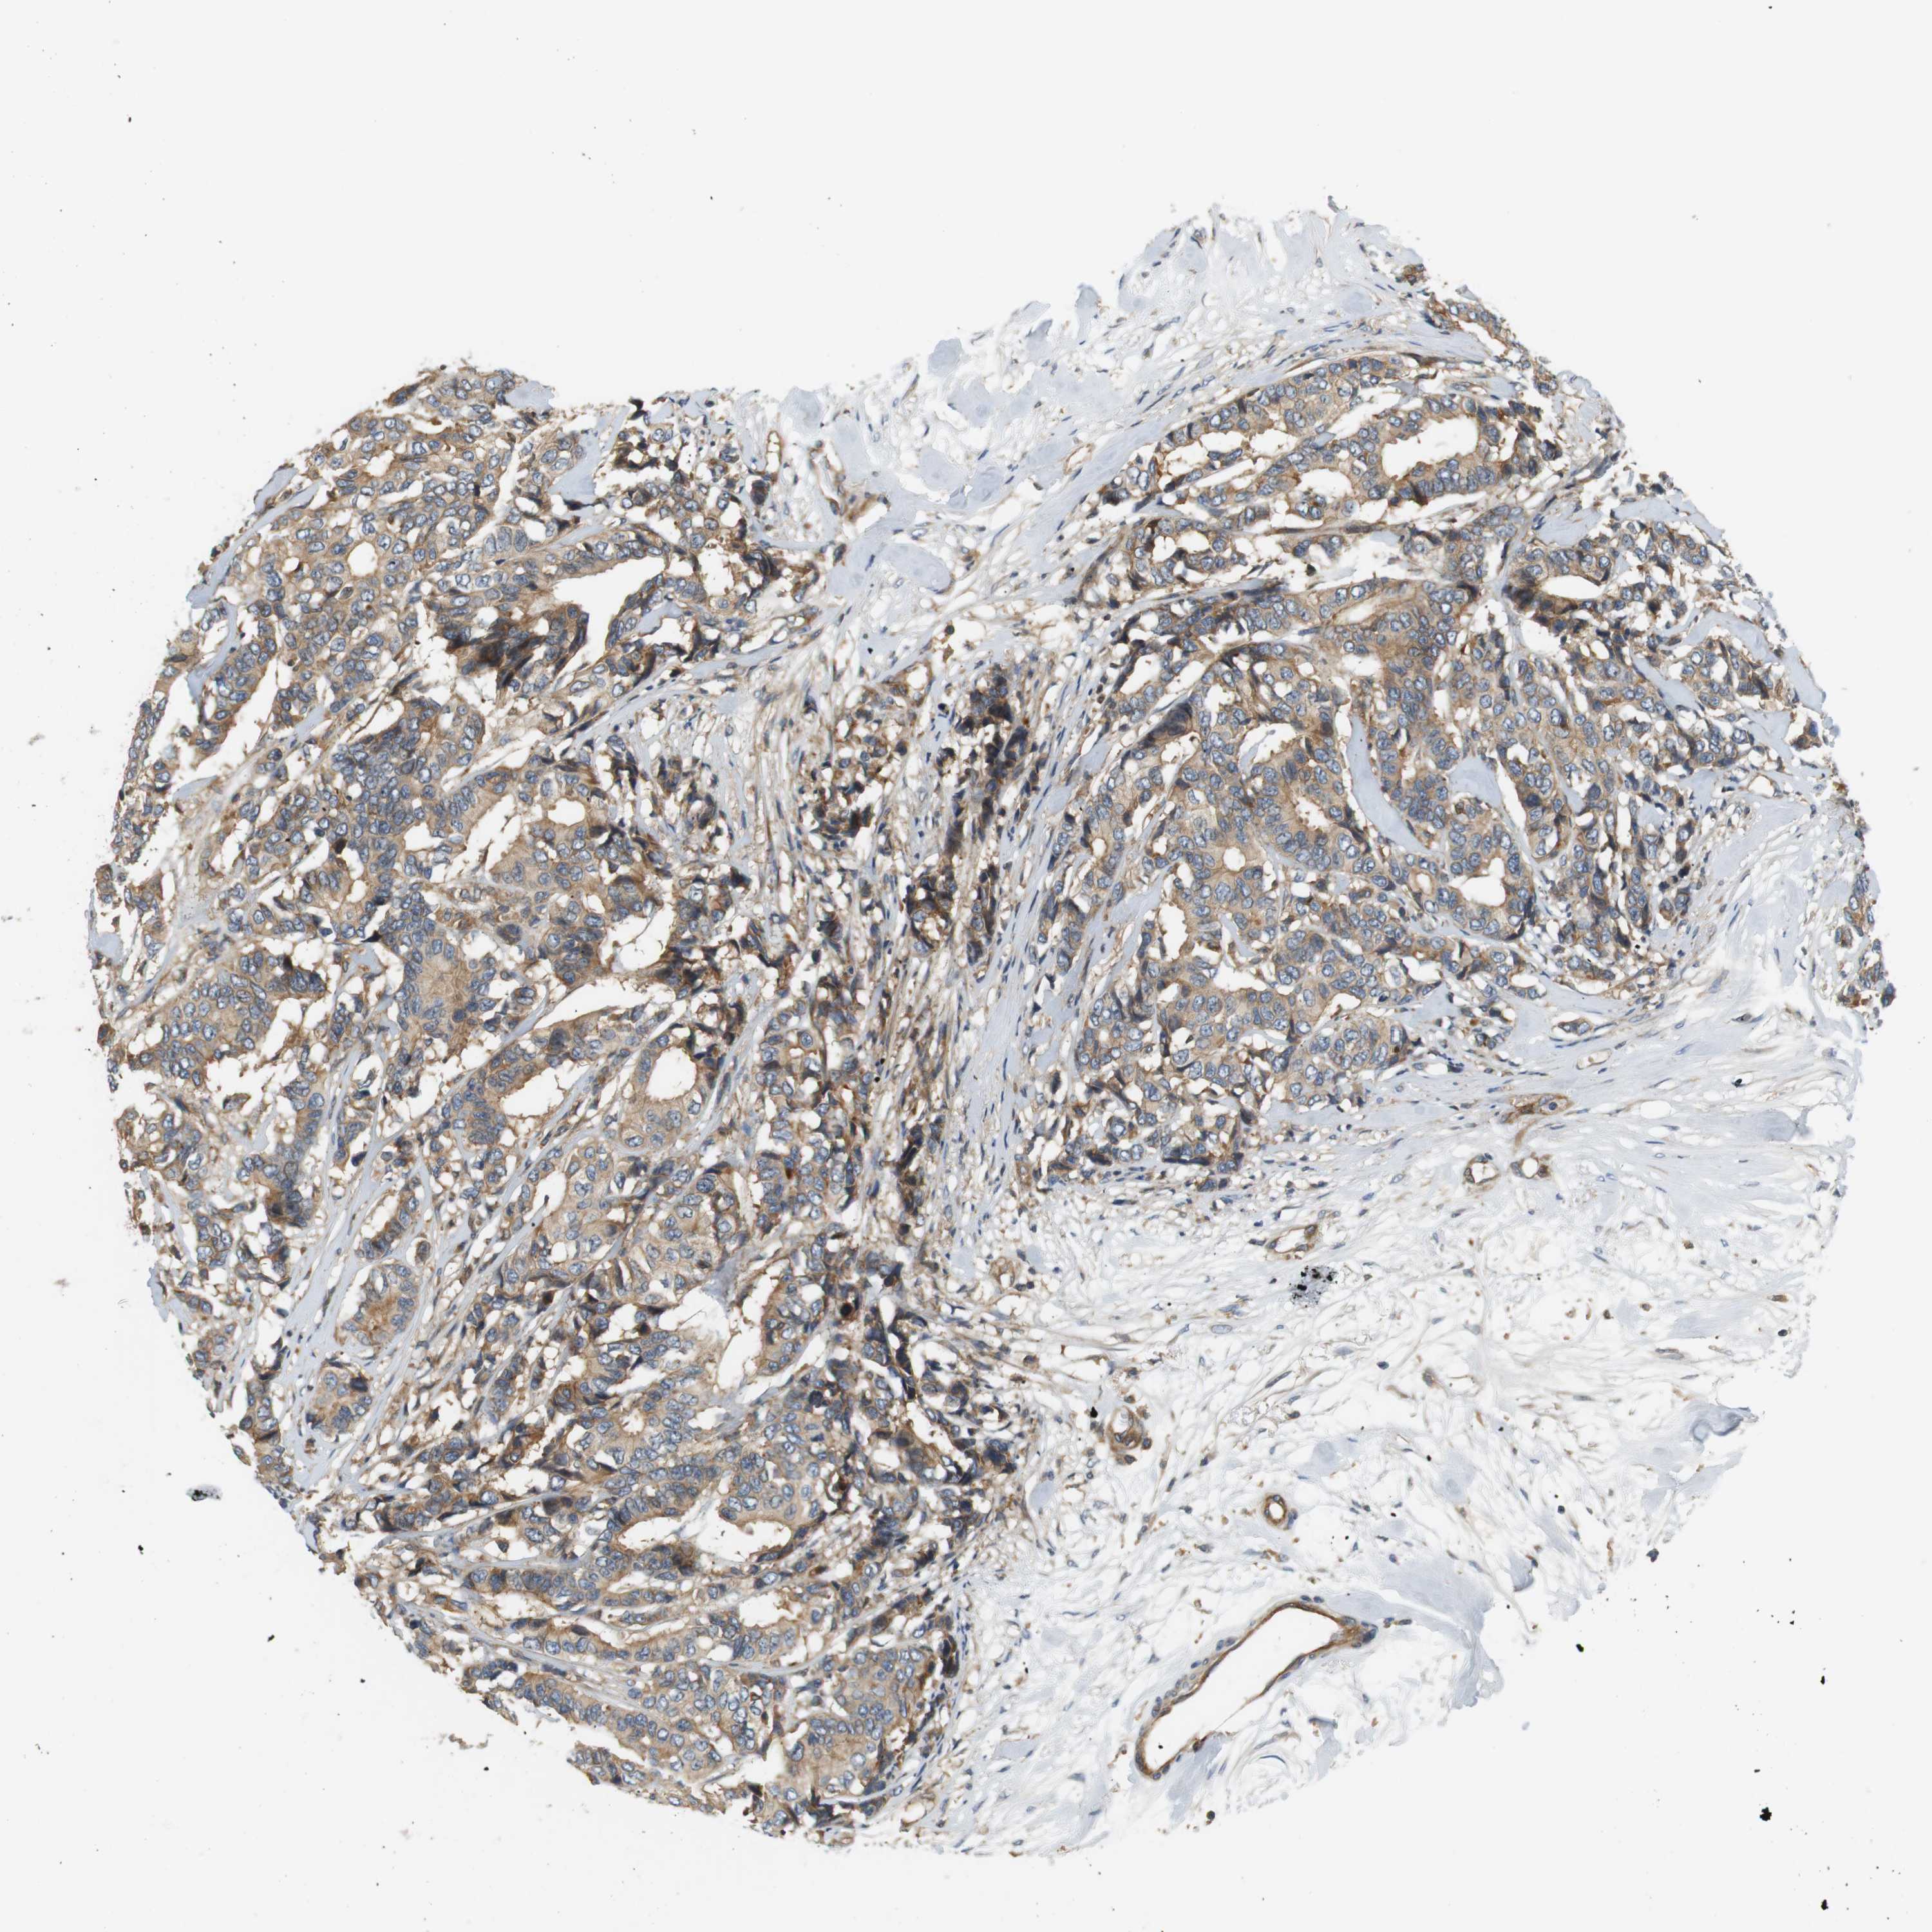

CANCER BREAST CANCER Show tissue menu

BRCA TCGA BRCA VALIDATION PROTEIN EXPRESSION